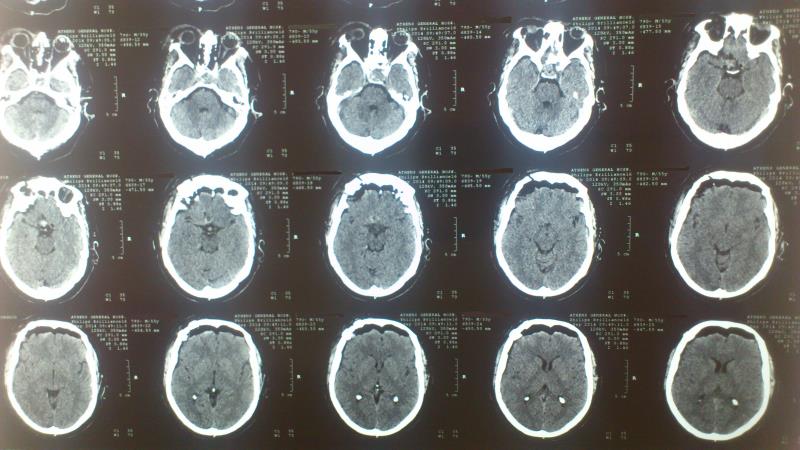

Ασθενής   55 ετών  ο οποίος είχε υποβληθεί  προ 3μήνου σε ενδοσκοπική διασφηνοειδική αφαίρεση μακροαδενώματος υπόφυσης  ( αδύνατη λόγω σκληρής σύστασης του όγκου η αφαίρεση του υπερεφιππιακού τμήματος του όγκου) προσήλθε στην κλινική μας  με σκοπό την αφαίρεση  του υπερεφιππιακού τμήματος του όγκου  δια υπερόφρυας τομής δέρματος και δεξιάς mini orbitozygomatic keyhole approach.  Η μετεγχειρητική του πορεία ήταν ομαλή με περαιτέρω βελτίωση των οπτικών του πεδίων ( αρχική μικρή  βελτίωση μετά την ενδοσκοπική διασφηνοειδική προσπέλαση ) και ο απεικονιστικός έλεγχος ανέδειξε την πλήρη αφαίρεση του υπολειμματικού όγκου.

Μετεγχειρητικός απεικονιστικός έλεγχος